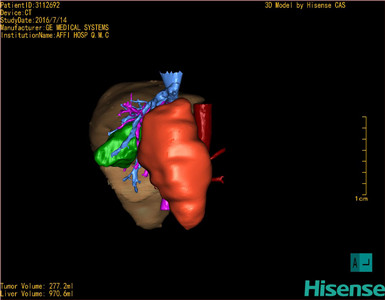

将0.625mm双源薄层CT资料的静脉期和动脉期Dicom格式文件导入海信CAS系统。

通过调节窗宽窗位调整CT序号,对肿瘤,肝实质,胆囊,下腔静脉,肿瘤,肝动脉、门静脉及肝静脉等进行三维重建;系统自动计算肿瘤体积和肝脏体积。

模拟手术操作,自动计算切除肿瘤体积。肝脏体积为970.6ml,肿瘤体积为277.2ml,肿瘤体积为肝脏体积的28.6%,通过比对60-70岁正常肝脏体积为1262.7±284.31 ml,通过术前模拟手术,精准判断切除后剩余肝脏体积能耐受,避免肝衰竭发生。

术前手术方案的规划。

术前三维重建:

重建图片